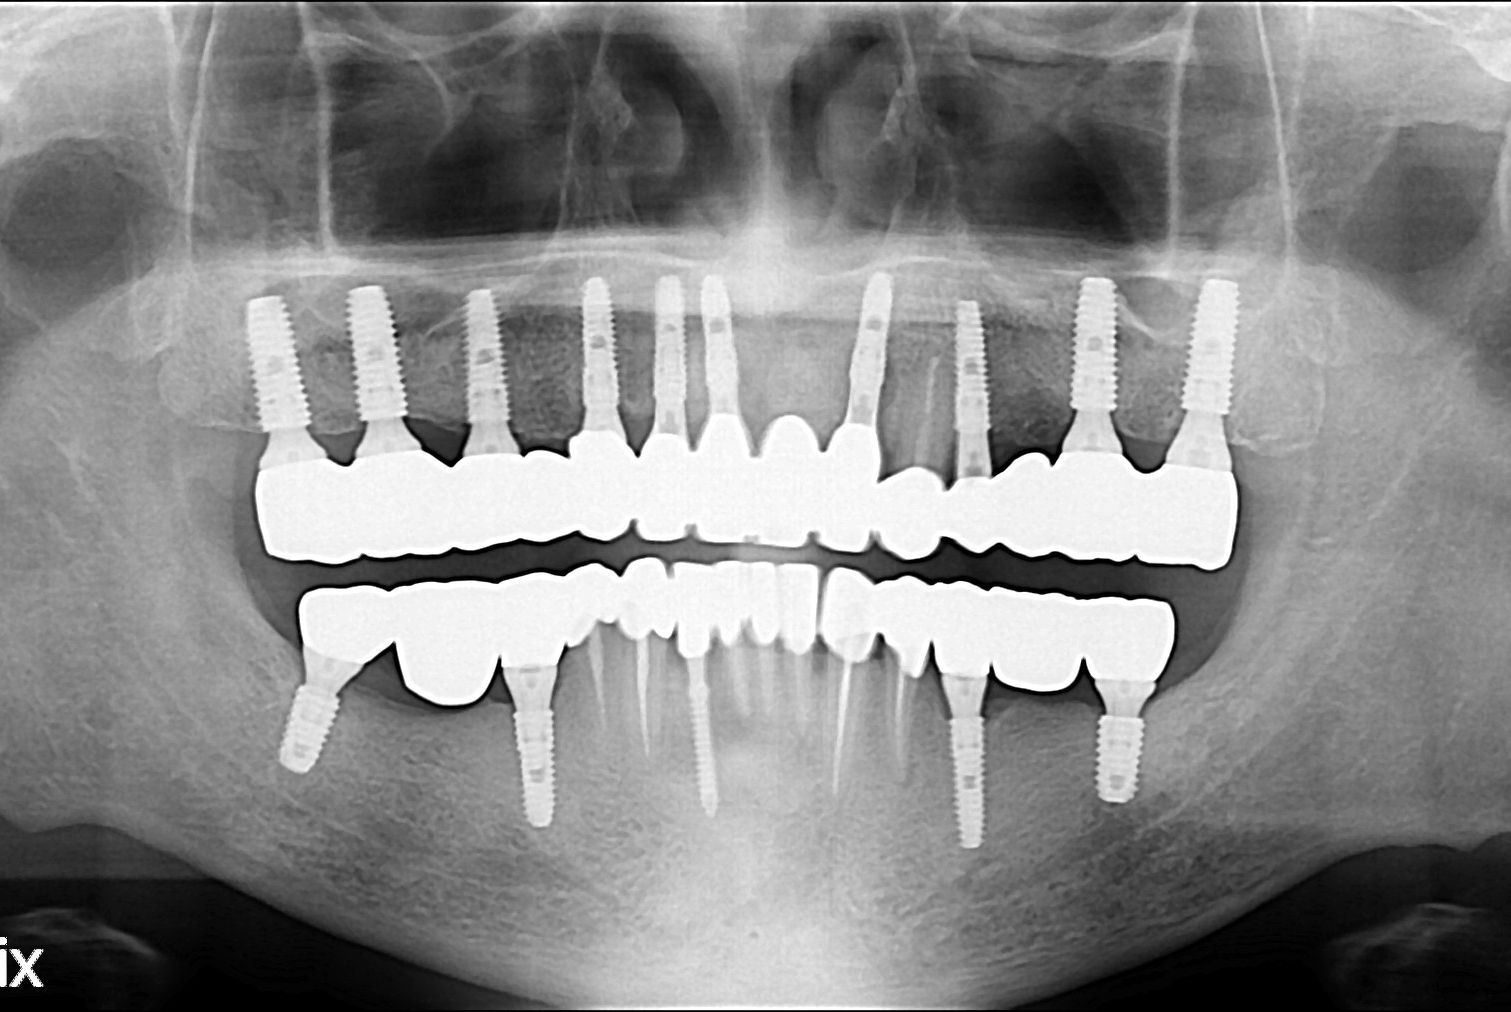

정철호 후.jpg

치료후 : 2019-12-04

세종치과는 많은 환자와 다양한 케이스를 바탕으로 항상 편안한 임플란트 수술을 제공하고자 노력하고,

오래동안 튼튼히 쓸 수 있는 임플란트 수술을 가장 큰 목표로 삼고 있습니다